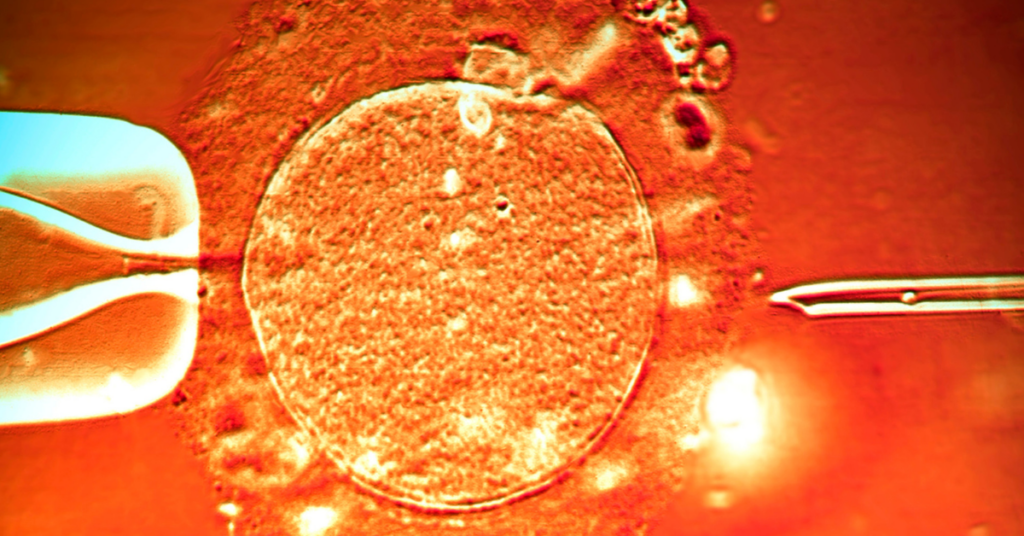

Svaka buduća mama razmišlja i proživljava svaki sekund, svaki bebin minut dok je u stomaku. Do skoro je teško bilo i zamisliti kako uopšte izgleda razvoj tog malog života, no savremene tehnologije sada to menjaju.

To čudo prirode, otelotvoreno u nastanku života tokom 40 nedelja, moguće je sada videtu u kratkom video-snimku u trajanju od četiri minute. I bukvalno se vidi svaki detalj, sve te fantastične promene na trudnici, ali i u njoj – od začeća pa do porođaja.

Tih promena mame obično nisu ni svesne, katkad traju bezgranično, ali kada se ceo taj period sažme u samo četiri minuta, rezultat je impresivan i apsolutno nikoga neće ostaviti ravnodušnim.

A kako izgleda kada cela trudnoća od devet meseci? Evo, baš ovako.